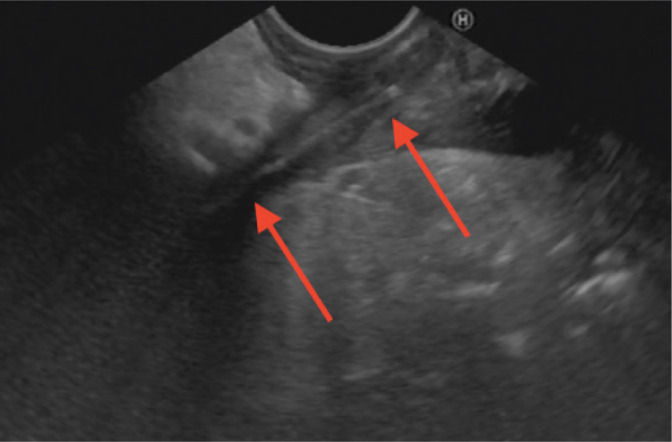

Transabdominal ultrasound, Aloka Alpha Prosound 6, straight arrow: stomach (pyloric part) transverse view, curved arrow: toothpick

Ultrasound: Hypoechoic, polycyclic lesion (35 × 28 × 50 mm) near the pancreatic body and tail.

Transabdominal US: Linear hyperechoic object (40 mm) from gastric antrum wall towards pancreatic body, surrounded by dense fluid collection, indicating a foreign body.